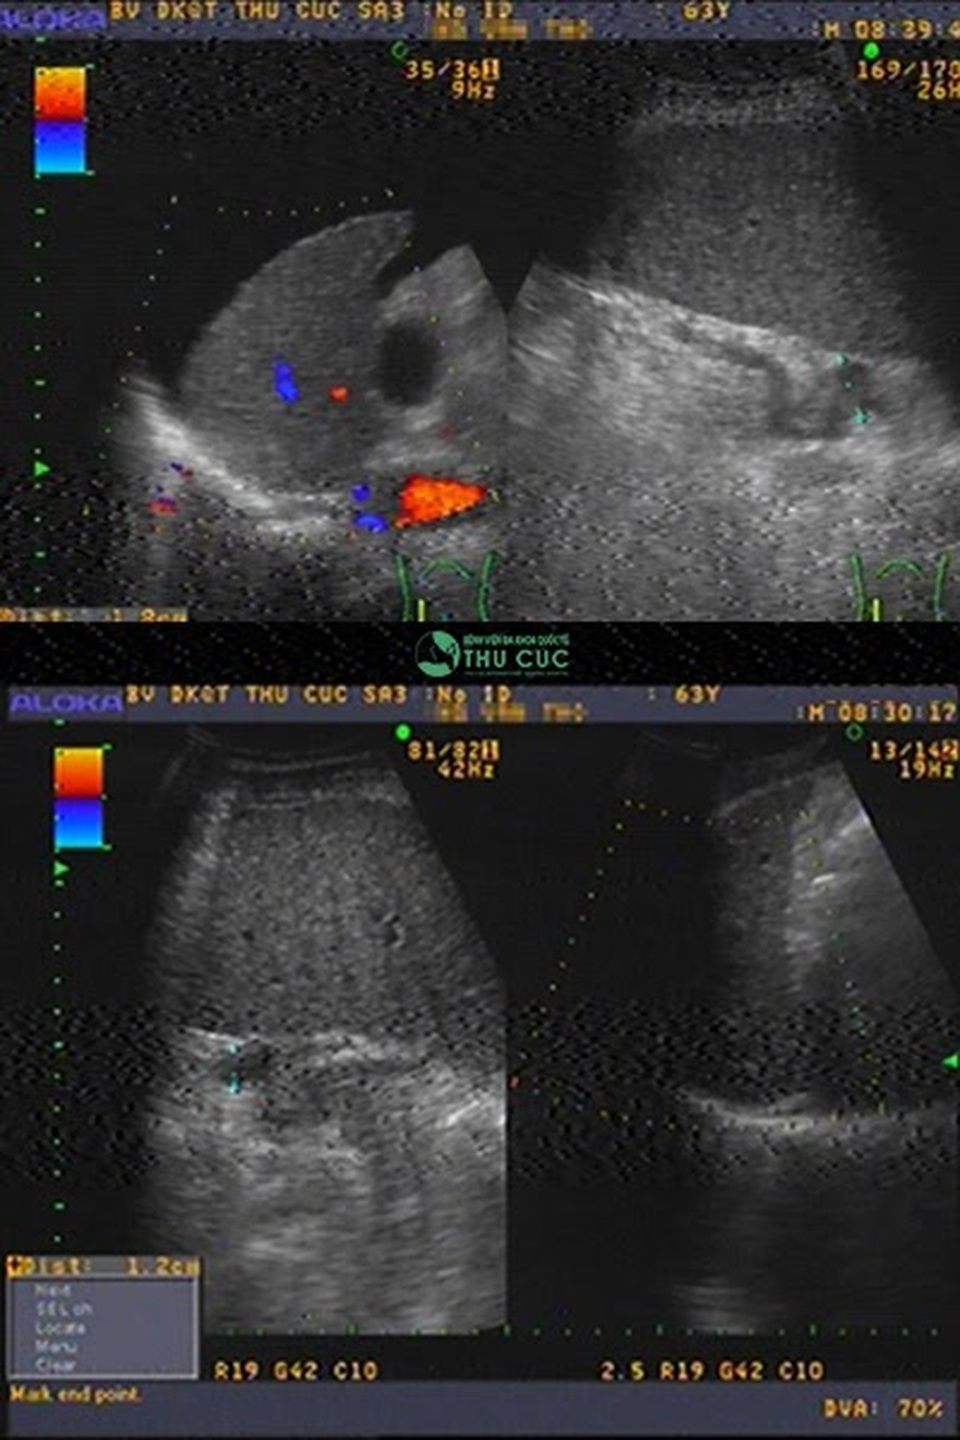

PGS Thành nhớ lại: “Ông T nhập viện trong tình trạng cấp cứu, tính mạng bị đe dọa nghiêm trọng. Sau khi thăm khám và làm các xét nghiệm, chúng tôi phát hiện trong ổ bụng ông T có rất nhiều dịch, thiếu máu và suy dinh dưỡng trầm trọng, chỉ số tiểu cầu, men gan, Albumin trong máu … ở mức rất thấp. Kết quả chẩn đoán, ông T bị xơ gan cổ trướng hay còn gọi là xơ gan giai đoạn cuối.”

Sau một tháng điều trị bằng phương pháp hấp thu dịch, dịch cổ trướng của ông T đã hết, chỉ số tiểu cầu tăng từ 37 lên 42 đơn vị, chỉ số Albumin trong máu tăng từ 23,8 lên đến 31,6 đơn vị, chỉ số men gan cũng tăng đáng kể.